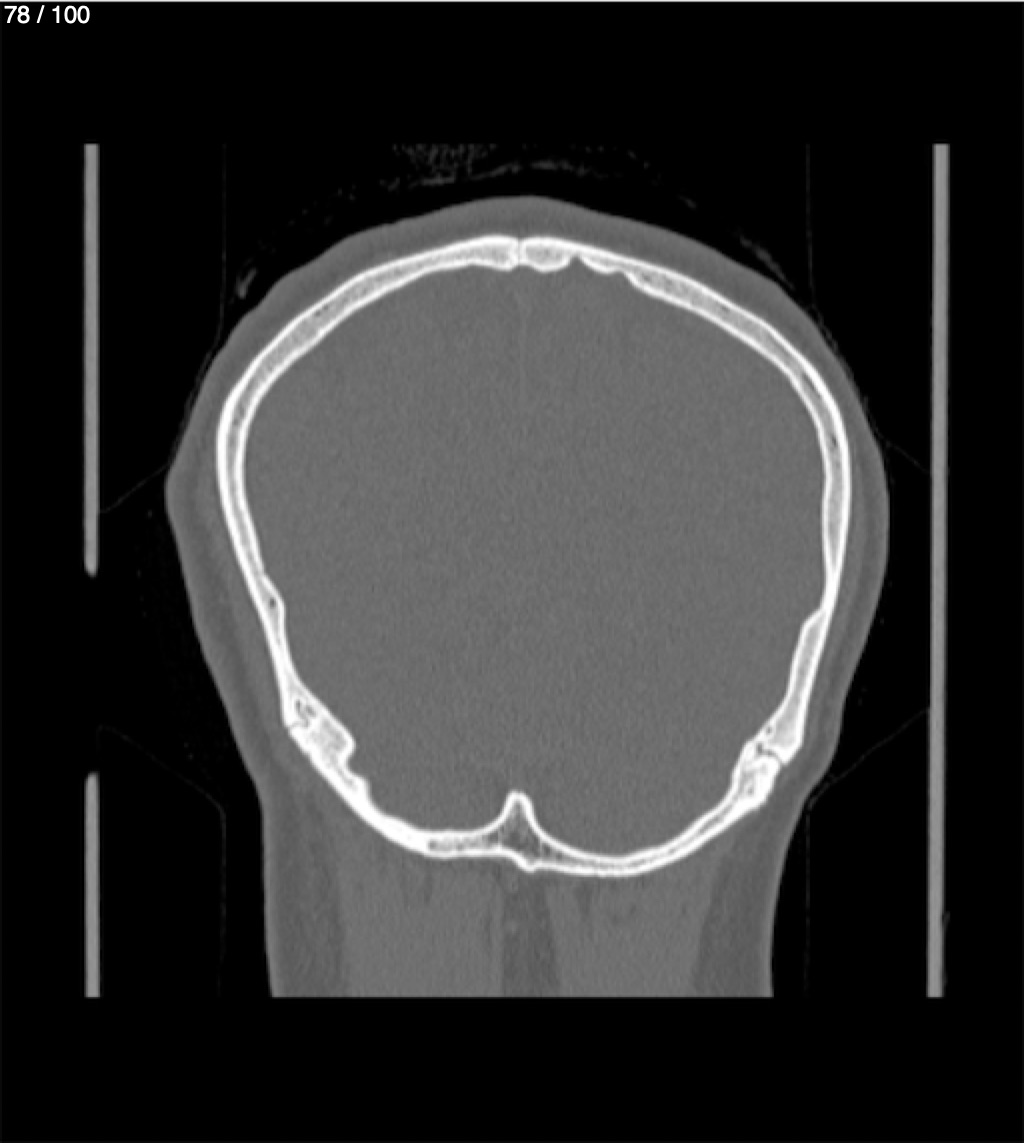

Yonelly Barrios Diaz 35A - T.C Craneo